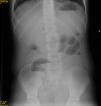

Caso 1Paciente varón con FQ DF508 de 11 años, afebril, con dolor y distensión abdominal, estreñimiento, con vómitos biliosos de 48h de evolución. En radiografía abdominal, se observa abundante material fecal en FID; la ecografía es anodina. Ante la sospecha de SOID, se pauta enema de N- acetilcisteína, con alivio parcial de síntomas, y aparición de deposiciones escasas blandas. A las 24h, bajo control radiográfico, se realiza enema opaco con Gastrografin®, con resolución del cuadro.